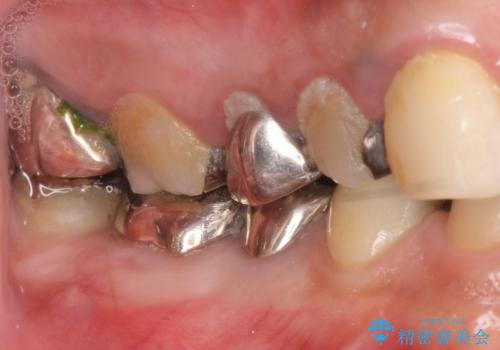

- 歯がない左側でものが咬めず、右側で咬むと歯が痛むので診て欲しいといらっしゃった方の症例です。

根尖病変が認められる歯は再根管治療を行い、歯根が破折していた左上4は抜歯しました。

インプラントは希望されなかったため、左側は1番から7番のロングスパンブリッジによる補綴を行いました。